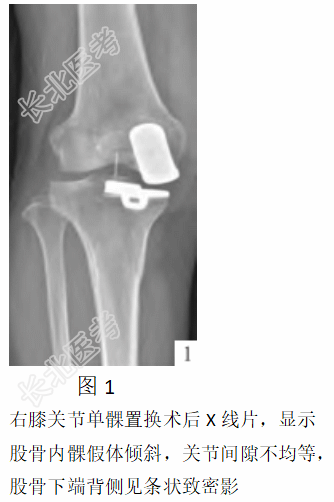

诊断:右膝骨关节炎。完善术前检查,在腰椎管麻醉下行右膝关节内侧单髁表面置换术(旋转平台假体),术后1周出院。出院时膝关节活动度0°~110°。1个月后某晚,患者在床上伸屈、旋转右膝关节时突然异响并剧烈疼痛,不能伸屈活动,遂再次就诊。行右膝关节X线检查显示(见图1):股骨内髁假体倾斜,关节间隙不均等,股骨下段背侧见条状致密影。查体:强迫体位,膝关节屈曲位,关节肿胀,膝关节活动度45°~60°。结合体格检查及影像学检查诊断为右膝关节单髁置换术后假体脱位,排除手术禁忌后,于2022年9月8日在全身麻醉下试行闭合复位术失败,遂取出假体,行右膝关节双间室置换术。术后右膝关节DR片显示假体位置良好。术后2周出院,出院时膝关节活动度0°~110°。术后随访10个月,患者未诉不适,右膝关节功能恢复良好。